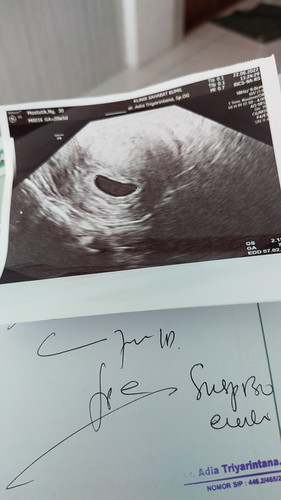

Bunda ada yg pernah ngalamin nggak .. kehamilan 7minggu ..janin masih terlihat samar

Kehamilan 2bulan

tunggu 2 minggu lagi bun.. kalo udah 9w seharusnya udah kelihatan janin & ada detak jantungnya